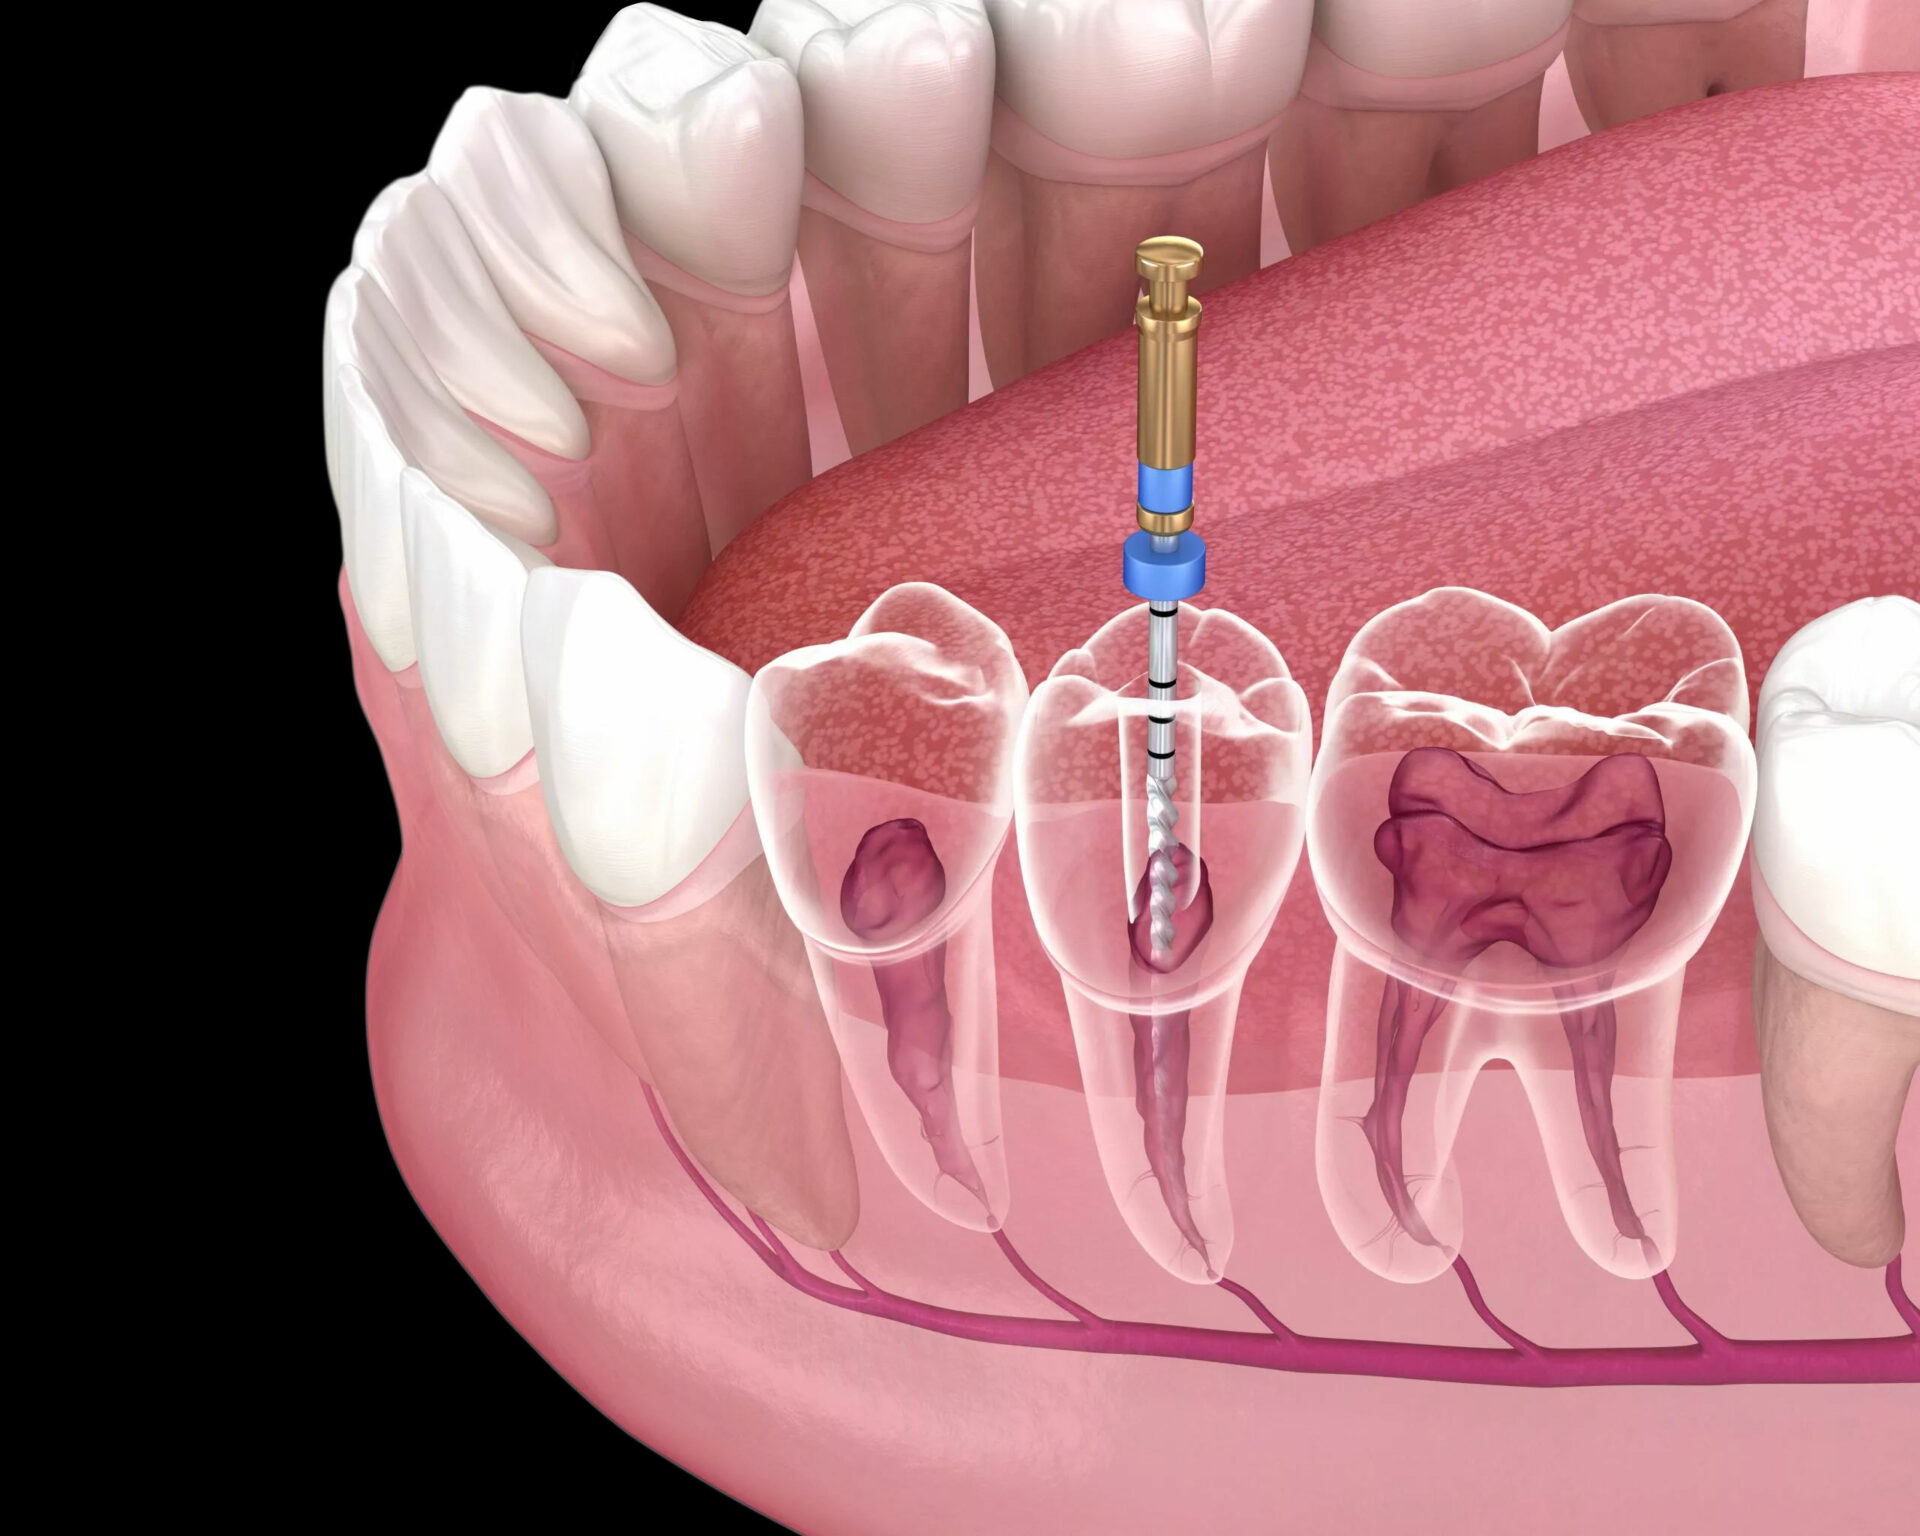

Root Canal Treatment

Relieves pain fast and saves your natural tooth with a smooth, comfortable procedure.